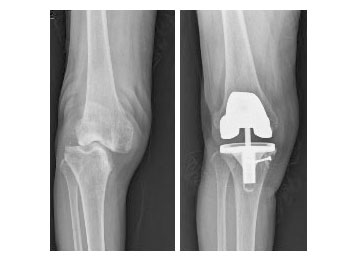

• 골결손을 동반한 관절염으로 인공관절치환술 사진

골결손을 동반한 관절염으로 인공관절치환술 시행